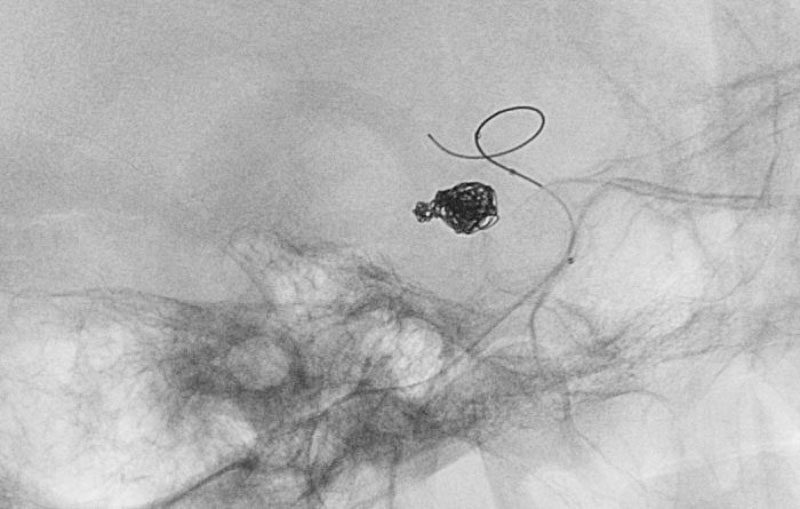

No.1187 手術中